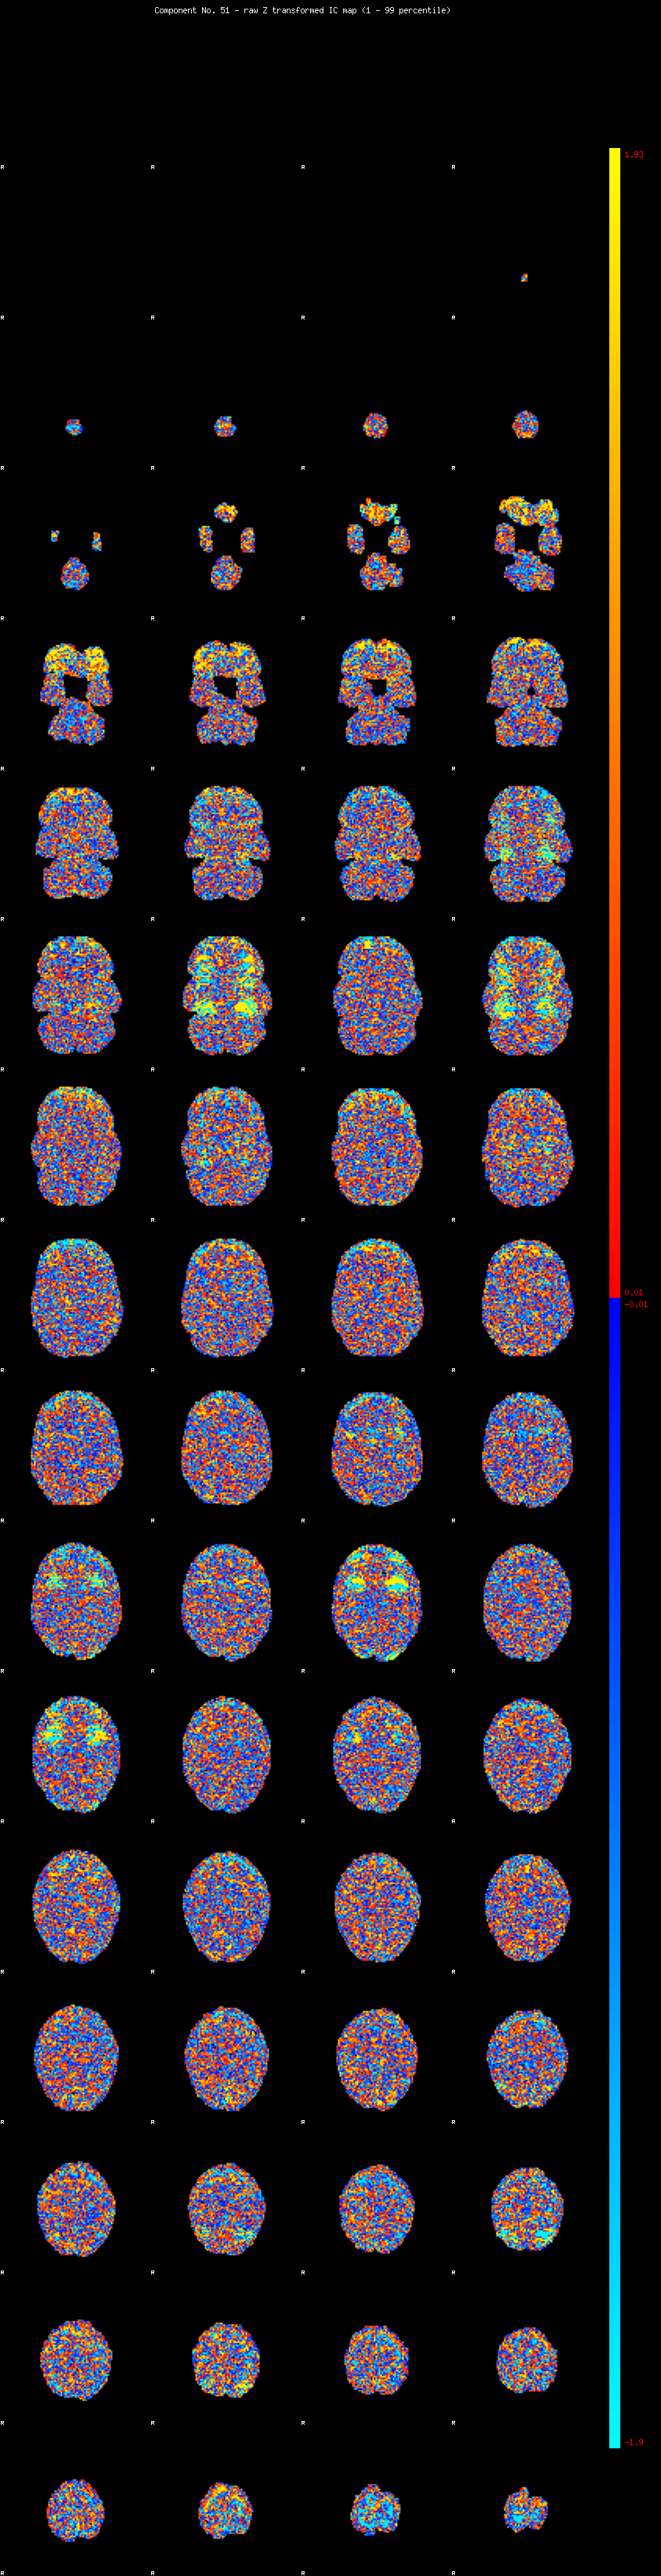

IC_51 Mixture Model fit

Means : 0.000000 2.646792 -2.650260

Vars : 1.000000 2.628951 2.679984

Prop. : 0.954702 0.024014 0.021284